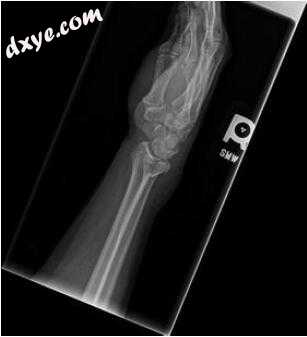

右腕的PA和侧位X线片显示背侧移位,关节内远端桡骨骨折(图6.1和6.2)。在局部血肿块下成功完成闭合复位,并将患者置于钳夹板中。在她的随访门诊就诊时,重复X线片显示她的掌侧倾斜失去了大约12度的背角(图6.3和6.4)。根据她的初始位移,残余位移,关节内受累和她的活动水平,决定进行切开复位和内固定以改善其对齐。

图6.1损伤PA表现出明显的桡骨长度损失,实际上只是背侧角度,侧面投影更好

图6.2损伤侧向显示关节内粉碎的背侧角度。 请注意,相对较简单的图案在背侧具有较大的撞击和位移

图6.3减少后PA

图6.4减少后侧向X射线显示改善的排列,但月球似乎与背侧关节碎片略微背侧翻转